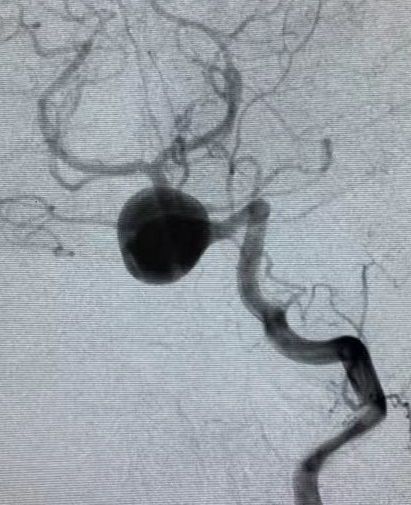

2019.5.25外院DSA

通过造影可以看到,动脉瘤主体位于右侧椎动脉,左侧椎动脉也有累及,不过左侧椎动脉PICA以远的部分纤细,考虑可以牺牲掉而不会影响基底动脉血供,但可以部分减少动脉瘤压力。左侧椎动脉为优势椎动脉,则应用PED装置保护并重建之。

经左椎动脉造影可见椎-基底动脉汇合部巨大动脉瘤,双侧椎动脉均有累及,以左侧椎动脉为主,右侧PICA与动脉瘤有一定距离,基底动脉稍受累及,AICA距离动脉瘤较近。